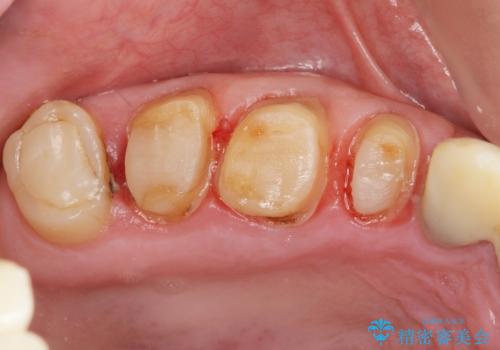

- 重度の歯ぎしり癖で歯がすり減り、見た目・噛み合わせの改善とこれ以上すり減る前の処置を希望され来院されました。

高さが短くなってしまった歯は、安定したクラウンを作るのが難しいため歯ぐきを下げる歯周外科を行ったのちに強度に優れるフルジルコニアクラウンで補綴治療を行います。

すり減ってしまった歯に対し、歯冠長延長術(歯周外科)を行うことで安定したクラウンを製作・装着することが出来ました。